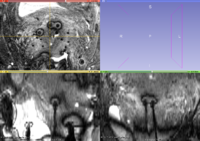

- Tip detection : We wrote a script using SimpleITK to extract and re-sample all the tip regions from images using needles from manual segmentation. These 115 cubical regions can now be used for data analysis (machine learning). As a first step, we built an average model (template) of the needle tips to be matched to new data sets, e.g. using convolution/correlation filters:

Needle Artifacts

Our hypothesis that the needle tip artifact show out in the average needle tip model could not be confirmed at this time: We need to use more cases with needle tip artifacts (instead of mixing with other cases from other MR sequences). Secondly, we should sort out the needle tips from the obturator needles. Third, the little cubic image around the needle tip could be registered to each other before averaging to fit more accurately. For now, the origin is registered, but the orientation could be improved. After convolution (SimpleITK) the average needle tip model with a patient MR image, this approach suffers from over-segmentation.